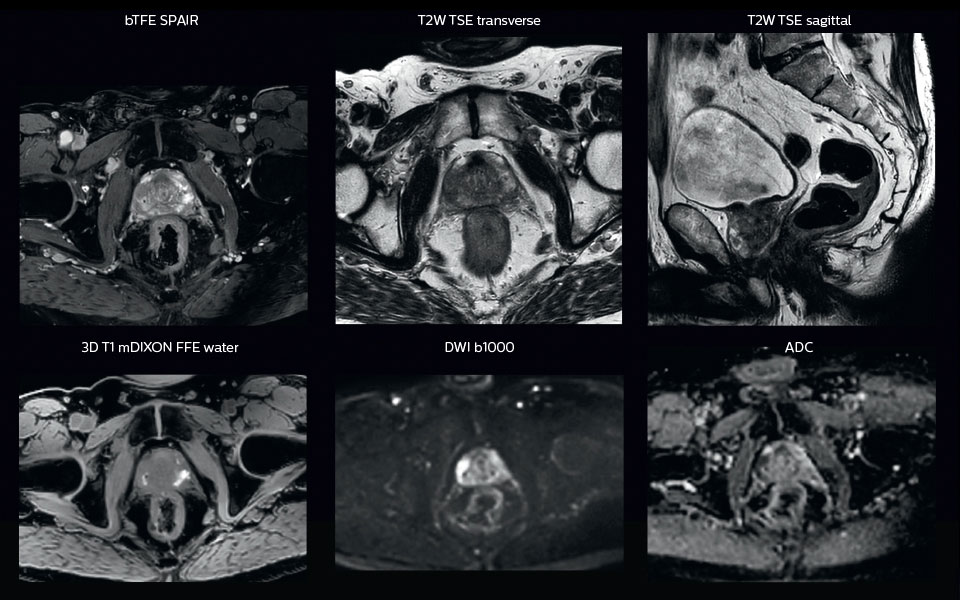

“In patients with a primary tumor in the head and neck area, we do use MRI in daily clinical radiation therapy practice to visualize the tumor and critical structures. This may be used to help sparing of critical structures, such as the parotid glands, submandibular glands, esophagus, optic nerves, brain stem and spinal cord [7]. And postoperatively we scan patients that have tumor growth along the cranial nerves for target delineation,” says Dr. Philippens.

“Because of the challenges posed by CT-MRI coregistration in this area with many degrees of freedom for motion, we image these patients in a radiotherapy mask. However, one disadvantage of using the mask is that a regular head and neck coil cannot be used; a dedicated coil solution would be needed for imaging with a mask.

For this we make use of flexible coils that we position close to the target area. This setup can also be combined with the anterior coil for a larger coverage and enhanced SNR.”

“We use pre- and post-contrast T1- and T2-weighted sequences with the fast and robust mDIXON method for fat suppression,” says Dr. Philippens. “Dynamic contrast-enhanced imaging is performed with high temporal resolution and low spatial resolution, to see the contrast agent uptake in the tumor. Diffusion weighted imaging is used qualitatively to see how the tumor extends into another structure, rather than for strict delineation.”

“In postoperative patients who have had tumor growth along the cranial nerves, we use T2-weighted gradient echo (FFE) on our 3.0T MR-RT scanner to show the nerves for target delineation and look to see if there is still tumor left.”